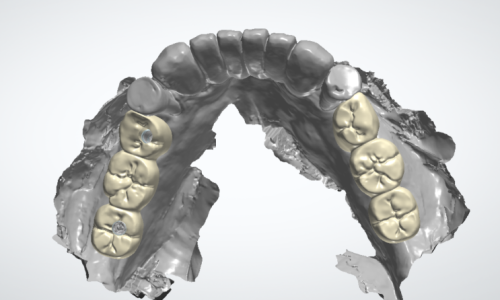

■ 5. 임시치아 체결

저희 세교동 치과 의 장점 중 하나인

임시치아 에 관한 내용을 기억하시나요?

픽스처와 치조골이

단단히 붙고 고정될 때까지

임시로 사용할 보철로서

수술 후 1개월 정도는

이렇게 힐링 어버트먼트 채로 있다가

어느 정도 회복이 되고 나면

그 위로 임시치아를 체결할 준비를 합니다.

임시치아는

어금니가 결손되었던 자리에 들어가는 보철인 만큼

위아래 어금니를 맞물었을 때

편한 위치가 어디일까 고려하여

제작하게 되는데요,

ATC 심미보철 세미나를 수료하고

CAD/CAM 마스터 클래스를 마친 제가

직접 디자인을 하고 체결까지 해드립니다.